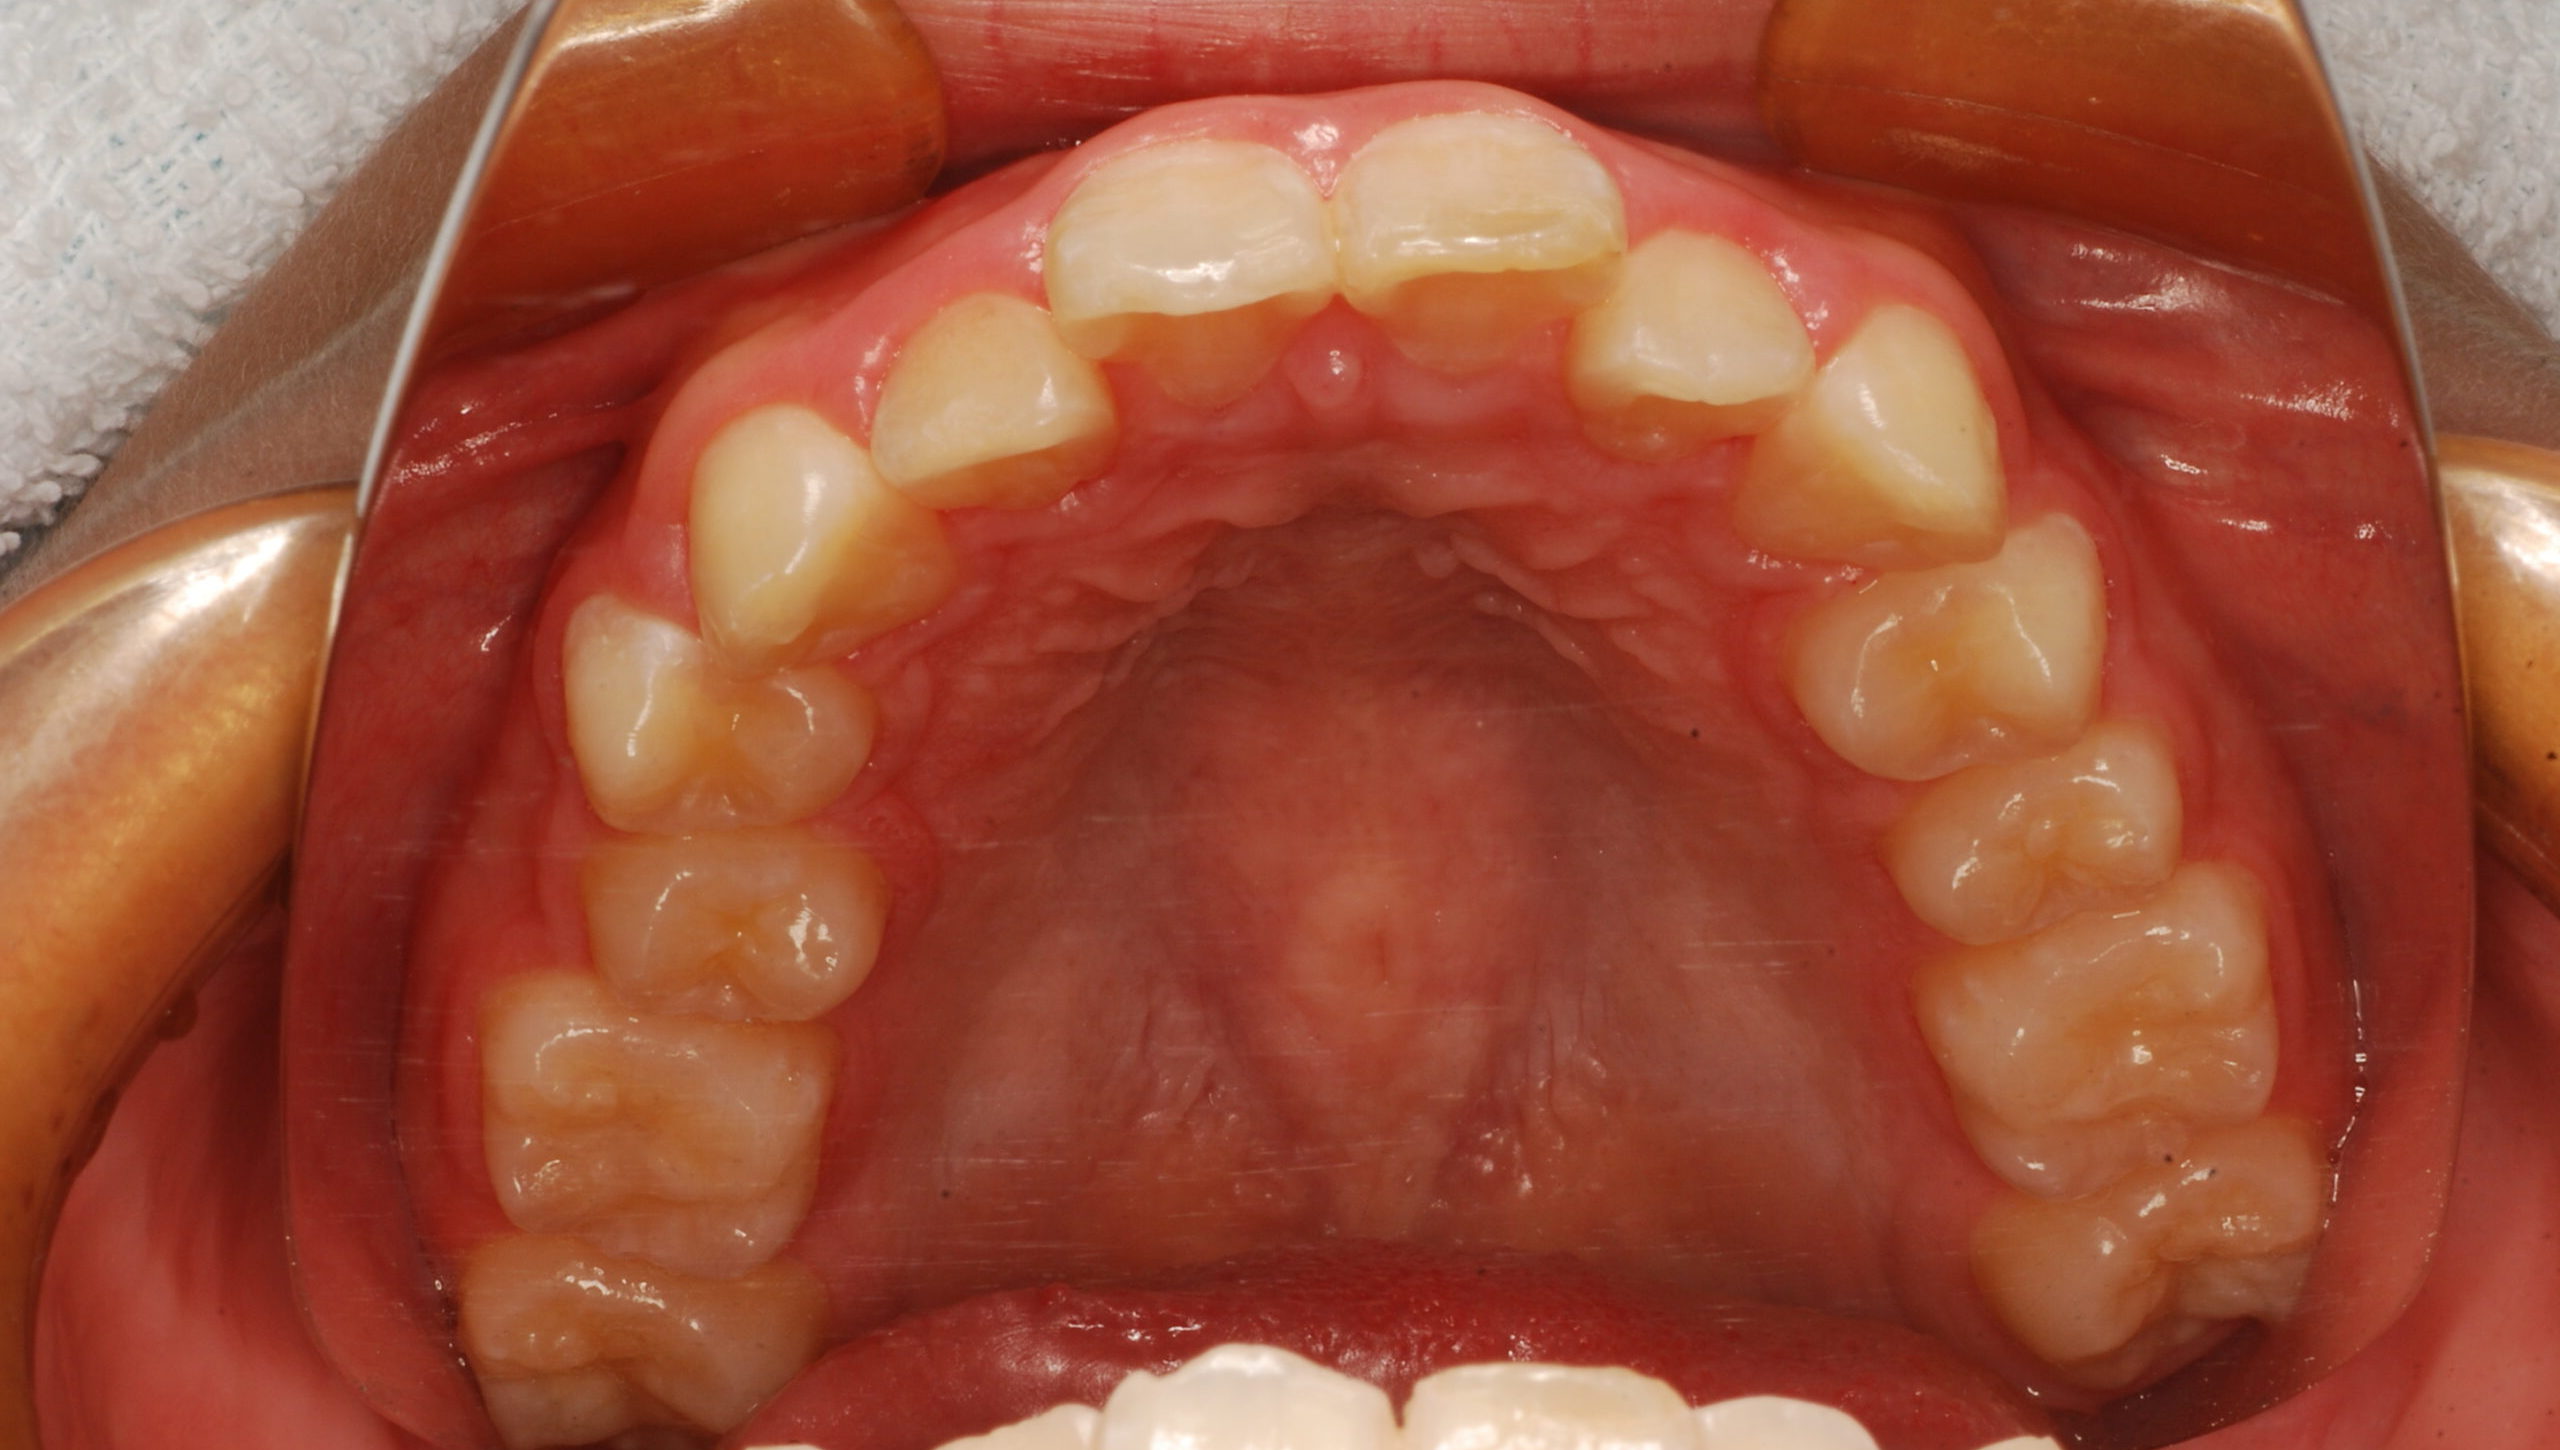

過蓋咬合・叢生 13歳男性

13歳9ヶ月 男性

治療後

【診断】叢生、過蓋咬合

【治療方法】上下両側第一小臼歯抜歯、ワイヤー治療期間3年間、上顎口蓋にTPA(トランスパラタルアーチ)を行いました。